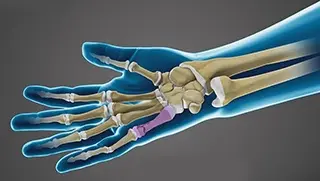

Fractures of the Hand and Fingers

Scaphoid Fracture

Boxer’s Fracture

Wrist Fracture Surgery